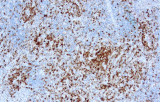

- Assegnazione del lignaggio & principali diagnosi differenziali: Fenotipizzazione cellule B vs cellule T (es. CD20 vs CD3), supportata da fattori di trascrizione nucleari delle cellule B come PAX5 quando i marcatori pan-B sono deboli/assenti.

- LLC/LLS: co-espressione caratteristica di CD5 e CD23 nelle cellule B CD20+ (l'interpretazione richiede consapevolezza del pattern perché sono presenti cellule T reattive).